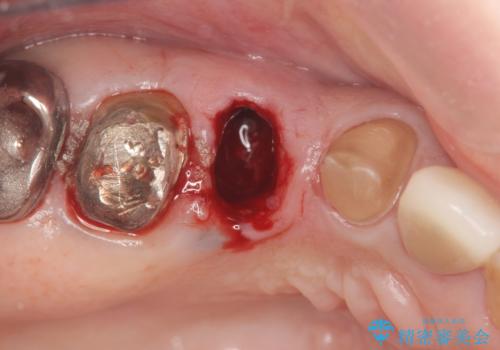

- ぐらぐらする小臼歯の治療を求めて来院されました。

X線検査、歯周組織検査より、歯は割れてしまい周囲の骨が高度に吸収してしまっている状態でした。

合わせて周囲の根尖病変や銀歯を治療するためにインプラントではなく、ご相談の上ブリッジ治療を行う治療計画としました。

また単純に抜歯のみを行うと歯ぐきが大きく凹み、ブリッジの清掃性が損なわれることが予想されるため、抜歯時に歯槽堤保存術を行い

清掃性の高い仕上がりとなるよう配慮しています。